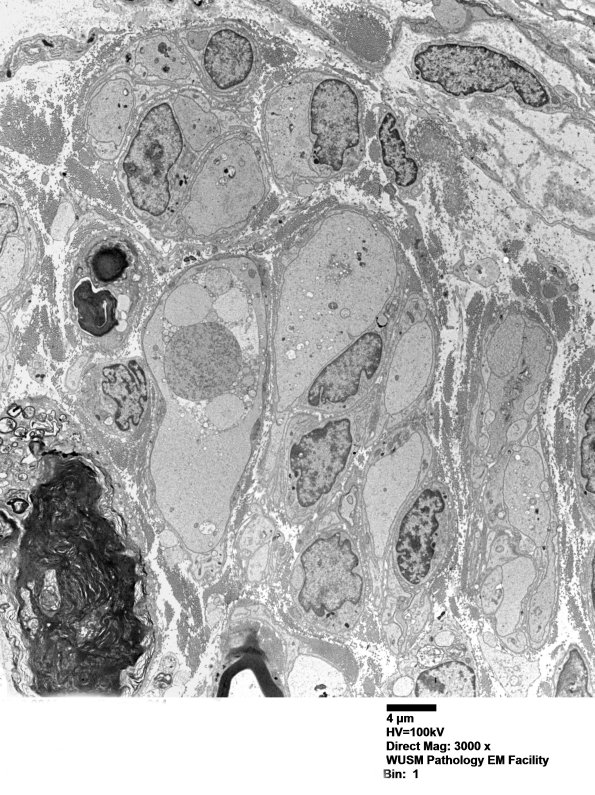

12B1-5 I have included electron micrographs in this section of focal axonopathy in which there is intra-axonal organelle accumulation and probably represents an area proximal to frank degeneration. (electron micrographs)